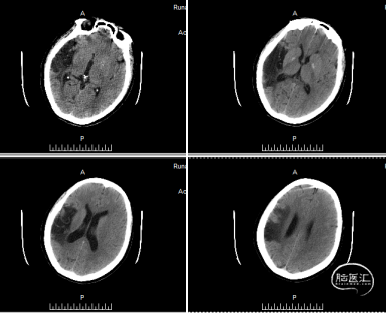

术后24小时复查头颅CT未见颅内出血。

患者术后24小时拔除气管插管,神志清楚,精神可,言语欠清,双侧瞳孔等大等圆,直径3mm,对光反射灵敏,颈软,心律齐,未闻及杂音,双肺呼吸音稍粗,未闻及干湿性啰音,右侧上下肢体肌力4级,左侧肌力5级、肌张力正常,双侧巴氏征阴性。术后24小时 GCS:15分,NIHSS:2分,mRS:1分。

术后15随访情况:7天后患者NIHSS改善。2周后随访,患者无明显肢体功能障碍,mRS评分为0分。